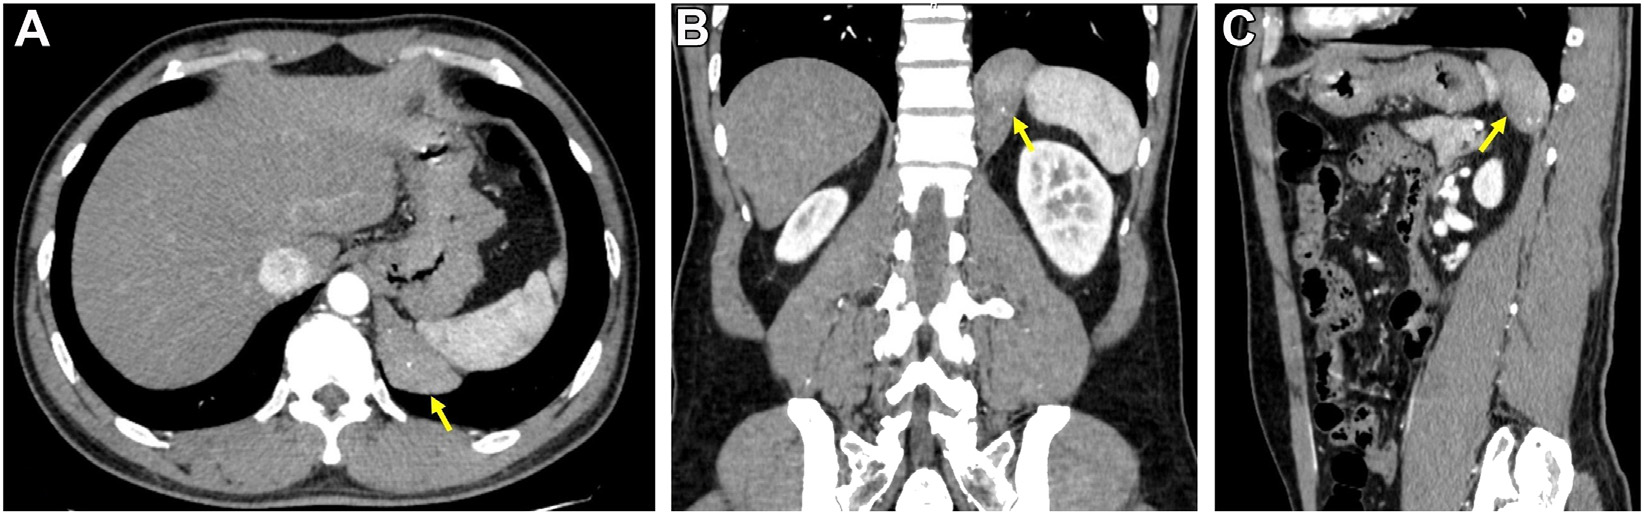

胸腹对比增强CT扫描显示左侧膈脚有一个6×5cm的椭圆形肿块(图2)。边缘清晰,轻度增强。肿块内可见多处结节状钙化。

图2 轴位(A)、冠状位(B)和矢状位(C) CT扫描图像